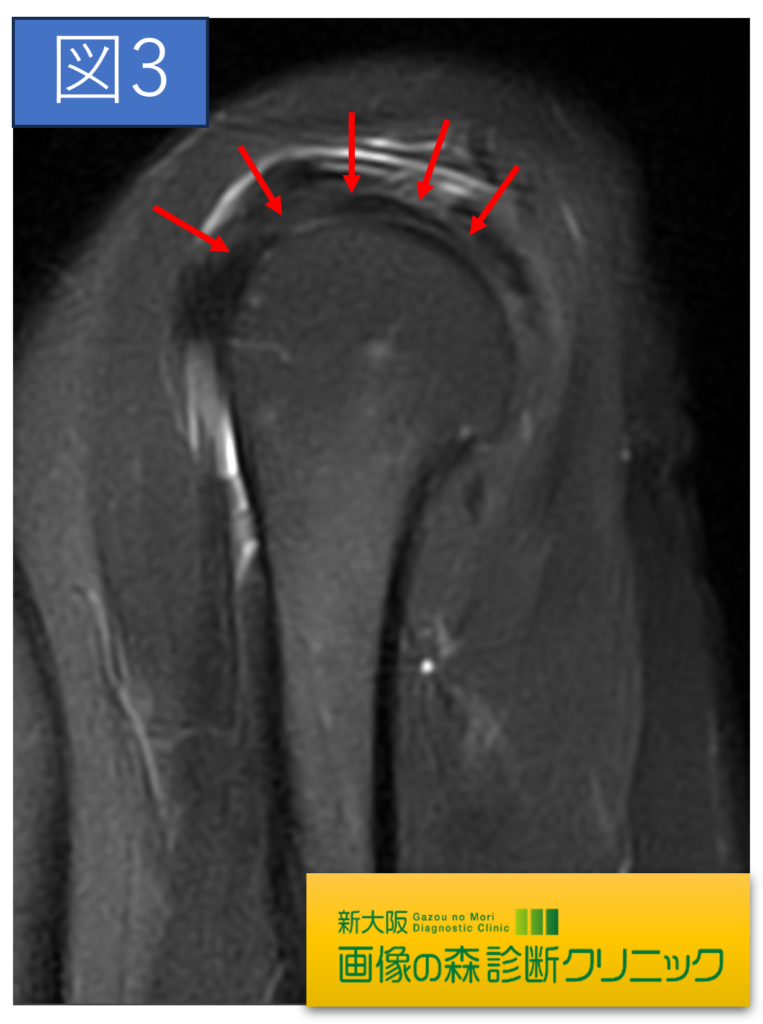

肩関節正常画像(矢状断像)

肩関節症例画像(矢状断像)

症例画像から図1~図4は棘上筋腱の画像です。□内に棘上筋腱の損傷を示します。正常では靱帯や腱は黒く描出されますが、損傷では白く高信号に描出されます。棘上筋腱損傷は、加齢による変性や転倒・スポーツ・仕事などによる外傷が原因となります。

症例画像から図1~図4は棘上筋腱の画像です。□内に棘上筋腱の損傷を示します。正常では靱帯や腱は黒く描出されますが、損傷では白く高信号に描出されます。棘上筋腱損傷は、加齢による変性や転倒・スポーツ・仕事などによる外傷が原因となります。